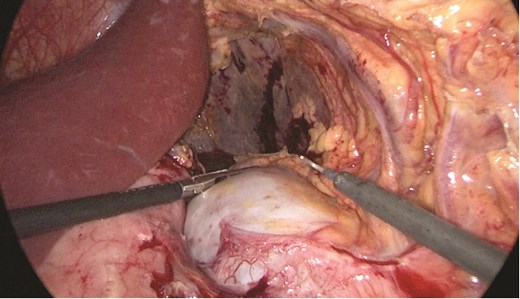

Multidisciplinary discussion was held to evaluate the most appropriate course of action for the patent condition, and the consensus was reached to pursue embolization as a first intervention. Embolization was performed by interventional radiology with no complications post-procedure, and the patient was optimized prior to her procedure. Patient was taken to the operating room in stable conditions. The spleen was enlarged around 20 cm. Inferiorly, the omentum and part of the transverse colon was attached to the spleen (Fig. 3), so we freed the omentum from the splenic tissue. The dissection continued until reaching short gastric vessels and entering the lesser sac (Fig. 4). Once the lesser sac was entered, the splenic vessels were identified (Figs 5 and 6), the splenic vein was hugely dilated with multiple collateral branching vessels at the hilum. Gaining posterior mobilization of the vein was challenging. The splenic artery was tortuous from the insertion around itself (Fig. 7). After complete mobilization of the fundus, we elected to divide each vessel starting with the splenic artery so we can achieve full mobilization of the vein (Fig. 9). After controlling the splenic artery, the splenic vein was dissected proximal to the splenic hilum (Fig. 8). It was hugely dilated and its wall is thickened secondary to AV fistula. It was difficult to achieve circumferential dissection, so we decided at that moment to convert to laparotomy to complete ligating the vein and to retrieve the specimen (Fig. 10a and b).

The spleen inferiorly, attached to it the mesentery and the transverse colon.